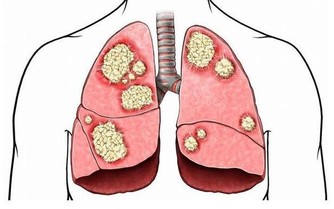

(2)皮膚發紅:肺結核

皮膚發紅是由於毛細血管擴張充血、血流加速以及紅細胞數量增多所致,在生理情況下見於運動、飲酒時。

疾病情況下見於發熱性疾病,如大葉性肺炎、肺結核、猩紅熱等,以及某些中毒,如阿托品等藥物中毒;紅細胞數量增多,如真性紅細胞增多症等也可引起皮膚發紅。

(4)皮膚暗紫:重度肺氣腫

由於缺氧,血液氧合血紅蛋白含量升高。

當還原血紅蛋白升高到每100毫升血液5克以上時,血液就會變成暗紫色。此時病人的皮膚、黏膜出現紫紺;皮膚出現暗紫的情況常見於重度肺氣腫、肺源性心髒病、發紺型先天性心髒病等。